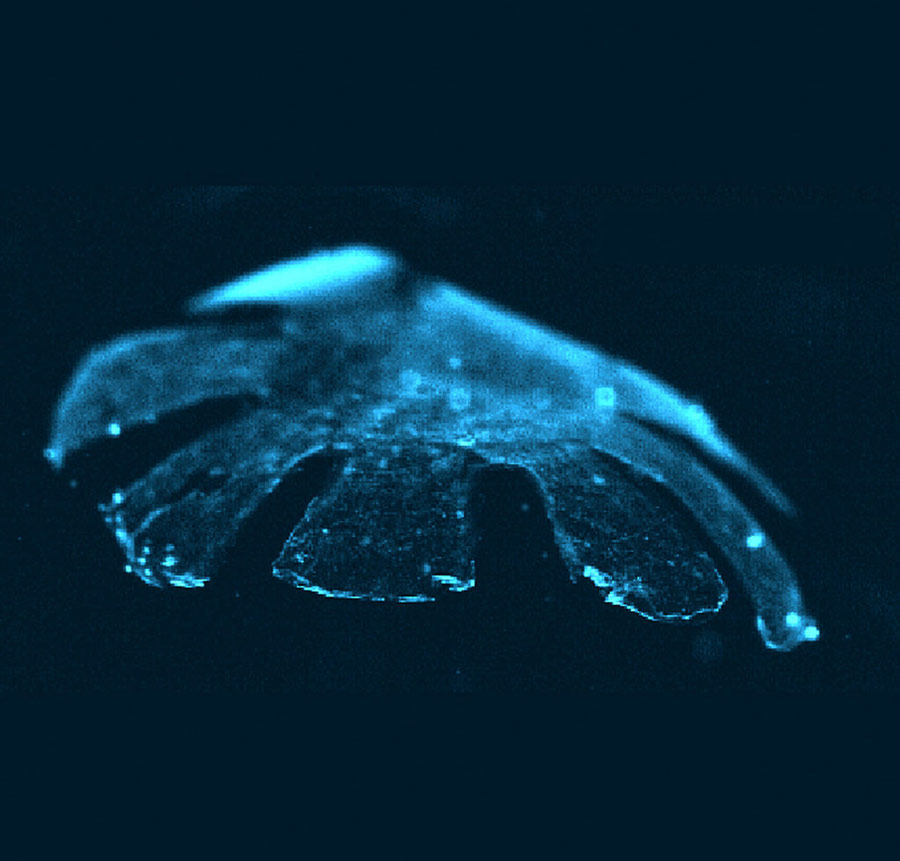

This bioengineered jellyfish is said to be another step towards helping patients with damaged hearts. Pictured here swimming in a pool of salt water, the robotic creature was created using a mixture of silicone and cells taken from rats' hearts. Although it isn't a living organism the "Medusoid" is very similar in muscle formation to that of a real jellyfish - meaning it can swim gracefully. Findings of the study were published by Kevin Kit Parker, bioengineer at Harvard University, in collaboration with a team of researchers at the California Institute of Technology. They hope the Medusoid technology brings them closer to creating new tissue, and eventually whole organs, for patients. "We're trying to become really good at building tissue for medical use, said Kit Parker. "This was a test." [Photo/CFP]